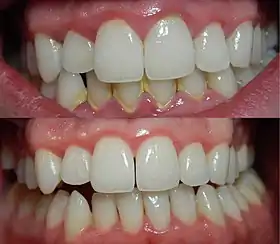

| A severe case of gingivitis | |